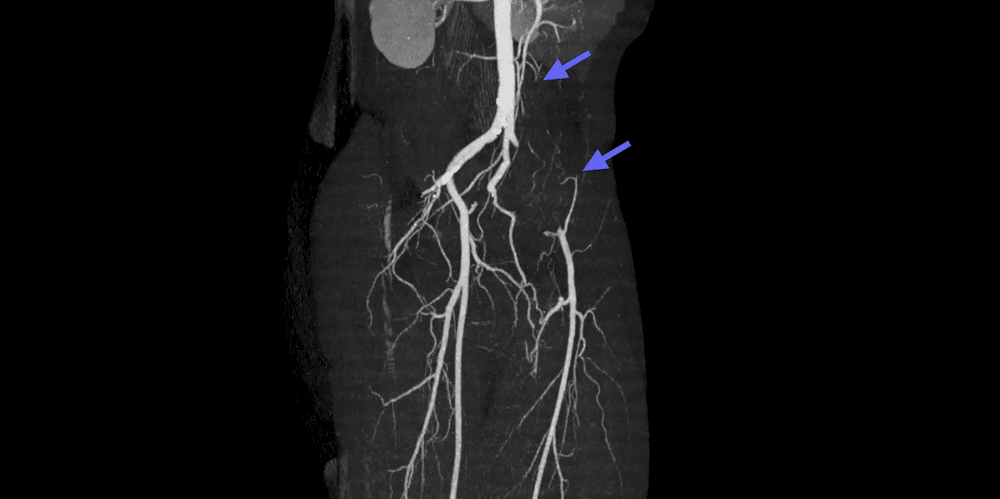

L'endofibrose de l'artère iliaque externe est une pathologie vasculaire rare qui affecte les athlètes d'endurance de haut niveau, en particulier les cyclistes.

CT